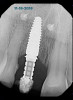

A 56-year-old female patient was referred for the evaluation of tooth No. 8 (Figure 4 and Figure 5). A periapical radiograph indicated that the tooth had undergone apicoectomy and received an excessively long post (Figure 6), and a cone-beam computed tomography (CBCT) scan of the site revealed a lack of buccal plate bone (Figure 7).

(6.) Pretreatment periapical radiograph.

Figure 6